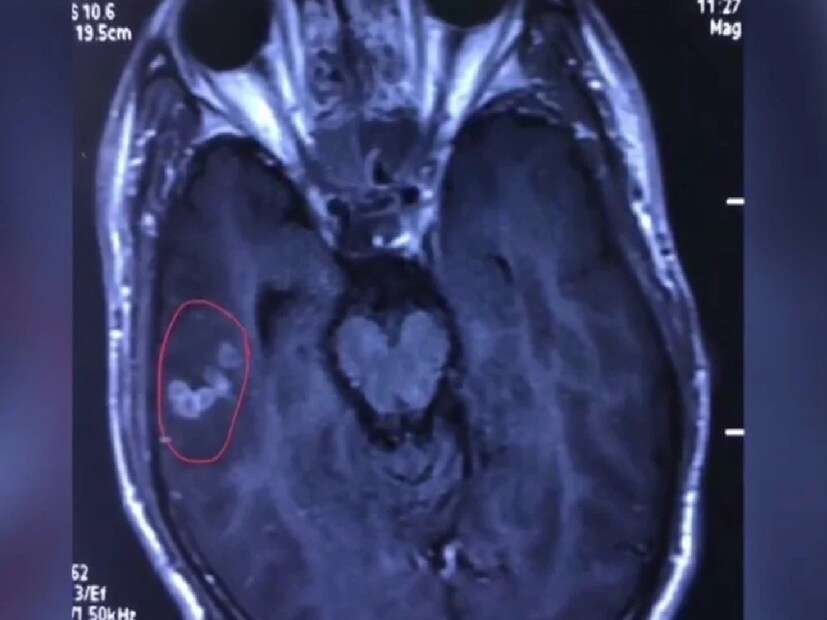

Brain Hemorrhage Symptoms: ব্রেন অ্যানিউরিজম একটি নীরব কিন্তু বিপজ্জনক সমস্যা। মস্তিষ্কের শিরা দুর্বল হয়ে গেলে তা ফেটে গিয়ে হতে পারে প্রাণঘাতী ব্রেন হেমারেজ। কিছু লক্ষণ আগে থেকেই দেখা দেয়, যেগুলি চিনতে পারলে সময়মতো চিকিৎসা সম্ভব, বিস্তারিত জানুন...

ব্রেন অ্যানিউরিজমের প্রধান লক্ষণ: হঠাৎ তীব্র মাথাব্যথা, যা আগে কখনও হয়নি এমন তীব্রতা নিয়ে আসে। দৃষ্টিশক্তি ঝাপসা বা দ্বৈত দেখা, চোখের পেছনে ব্যথা অনুভব হয়। ঘাড়ে টান বা শক্ত হয়ে যাওয়া: কোনো স্পষ্ট কারণ ছাড়া ঘাড় কষ্টকরভাবে শক্ত হয়ে যায়। বমি ভাব বা দুর্বলতা: হঠাৎ মাথা ঘোরা, দুর্বলতা বা বমির ভাব। অজ্ঞান হয়ে যাওয়া বা চেতনা হারানো: যখন অ্যানিউরিজম ফেটে যায়, তখন ব্যক্তি অজ্ঞান হয়ে যেতে পারেন।